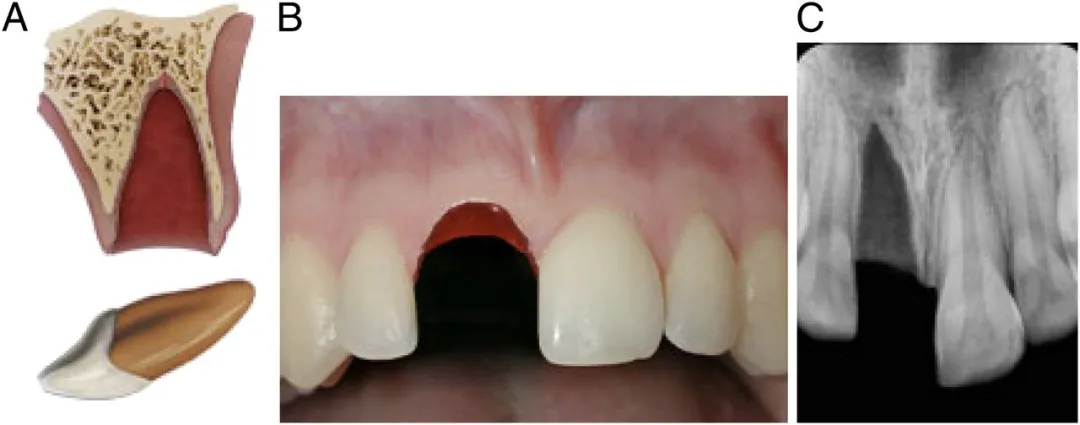

2、牙齿摔断

牙齿摔断依旧需要家长先找到掉的那半截牙,不过不用考虑保持细胞活性,所以不用泡牛奶了,找不到掉牙也没关系,尽快送医。

断牙治疗主要看断开的位置有没有暴露牙神经,分牙冠折断、牙根折断和冠根均折断等三种类型。

没有暴露牙神经,处理就比较简单。只需将牙釉质断面较锐利的地方磨光滑,不扎舌头即可。

也可以采用断冠再接的办法,把磕掉的那半截牙冠再粘回去。

如果牙齿摔断之后,牙冠碎了或者找不到了,就在保护牙髓之后,用材料对牙齿进行修复。